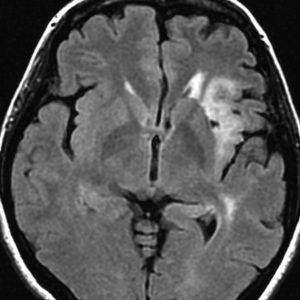

若い女性の左前頭葉から島回,側頭葉を侵す腫瘍で,てんかん発作で発症し,開頭生検 biopsy しました。

一部で,細胞密度が高く,核の腫大とクロマチンの増量,核間距離の短縮があり,核分裂像が認められ,MIB-1染色率が10%です。組織学的には退形成性乏突起膠腫グレード3とされました。

IDH変異あり,1P/19q欠失あり,ATRX変異なしです。

乏突起膠細胞系グリオーマなので,放射線治療の高線量領域はあまり広くとりません。

IMRT Simultaneous Integrated Boost (SIB)で,FLAIR高信号の領域に54グレイ27分割,周囲仮定浸潤領域 generous local areaに46グレイを照射しました。

テモゾロマイド75mg/m2を併用しています。

左の画像は放射線治療直後のMRIですが,すでに腫瘍の縮小がみられます。

テモゾロマイドの維持療法は,24コース 2年間行い,それ以降は無治療としました。

照射後7年の画像です。腫瘍は縮小したまま,患者さんは無症状で経過しています。